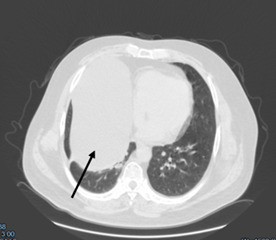

Предоперационные лабораторные исследования не показали каких-либо отклонений от нормы. Информативными были инструментальные исследования. На аксиальных КТ- изображениях грудной клетки и реконструкциях легких в нативном режиме от 07.10.2024: справа в проекции S4-5-8-9 сегментов определяется овальной формы патологическое образование с четкими ровными контурами, однородной структуры, плотностью до 6 ед.Х., размером 19.5х10.5 см.

Рисунок 2. КТ грудной клетки во фронтальной проекции (киста перикарда указана стрелкой)

Рисунок 3. КТ грудной клетки в аксиальной проекции, срез на уровне 8 ребра (киста перикарда указана стрелкой)

Легочный рисунок деформирован, усилен. ЭКГ от 17.10.2024: ритм синусовый, правильный. Частота сердечных сокращений 78 ударов в минуту. Нормальное положение электрической оси сердца, гипертрофия левого желудочка. Спирография от 18.10.2024: нарушение дыхательной функции легких рестриктивно - обструктивного типа: рестрикция - легкой степени, обструкция проксимального отдела - средней степени. ЭХО КС 17.10.2024 год - Аортосклероз. Дилатация левого предсердия. Незначительная гипертрофия левого желудочка. Диастолическая дисфункция левого желудочка по 1 типу. Эпикардиальная жировая прослойка превышает допустимое значение (8мм). УЗИ ГДЗ 17.10.2024 год - гепатомегалия. Жировой гепатоз печени S-1. Липоматозные изменения поджелудочной железы. Солидное образование брюшной полости без четкой органопренадлежности. Правосторонний гидроторакс.

В нашем случае пациент не предъявлял каких-либо жалоб, ни со стороны дыхательной системы, ни со стороны сердечно-сосудистой системы. Подозрение на кисту возникло при прохождении рутинной обзорной рентгенографии грудной клетки, что послужило отправной точкой в истории его болезни. В дальнейшем использовался золотой стандарт диагностики кист перикарда – компьютерная томография грудной клетки. Однако, даже это не позволило поставить точный диагноз, в связи с чем было произведено оперативное вмешательство с диагностической целью. Выбор пал на миниторакотомию в связи с размерами образования: 19.5х10.5 см по данным КТ. Фактический же размер образования составил 20.0х14.0 см, а объём – один литр. Оперативное вмешательство выполнено без особых технических трудностей, время операции составило – 95 минут. Интраоперационно заключительный диагноз не вызывал сомнений, а гистологическое исследование препарата подтвердило его.